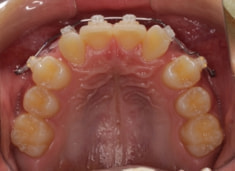

小児期ケース:反対咬合+上顎両側3番埋伏歯

(受け口+3番目の永久歯が左右両方とも埋まってしまい、はえてこない)

治療法:上顎急速拡大装置+クリアスナップ+フェイスマスク+上顎3番は開窓牽引CT写真にて位置確認

治療前